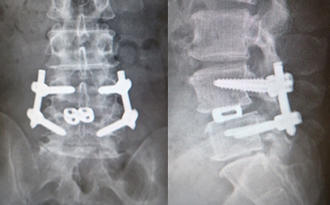

MIS-TLIF(低侵襲腰椎後方椎体間固定術) 椎間板にケージと言われるスペーサーが挿入され、また経皮的に椎弓根スクリューの挿入とロッドの連結がなされ、第4腰椎のすべりが矯正され固定されています。